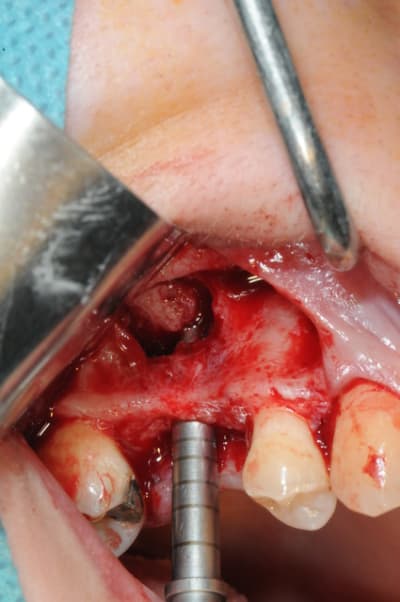

les premières photos, c'était ouverture par voie latérale

les suivantes;

- forage et transperçage de la crête sans aller trop loin...

- essayage pilier pour parallélisme

- forage à 3mm

- visualisation de la hauteur sous la membrane de Schneider

- utilisation d'un ostéotome diamètre 3.4 puis 3.8

(sous dimensionnement de diamètre par rapport à l'implant prévu :4mm)